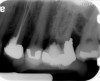

Fig 4. Preoperative radiograph showing aggressive external root resorption and thin dentinal walls.

Figure 4

Clinical procedure: Regeneration of the endodontic pulp space is indicated for cases with very thin dentinal walls and an open apex that is more than 1 mm in diameter radiographically (Figure 4). Disinfection of the root canal system is performed using sodium hypochlorite irrigation followed by a triple antibiotic paste dressing that is left in place for 1 week. At the second visit, ethylenediaminetetraacetic acid (EDTA) is used to condition the dentin walls, which results in the release of growth factors, and bleeding is stimulated in the periapical tissues (where stem cells are located), with the aim of filling the pulp space with a stable blood clot, which would serve as the scaffold. MTA is then placed at the canal orifice in contact with the clot to protect it from coronal microleakage (Figure 5 and Figure 6). In time, the clot should be replaced with a reparative tissue of variable composition, and the root walls should continue to thicken due to the deposition of a dentin-like material on the pre-existing root dentin27,28 (Figure 7 and Figure 8).